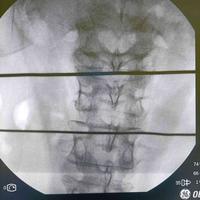

强直性脊柱炎

查看图片需登陆

强直性脊柱炎...

由 medjpg 发表于 2026-03-24 22:32